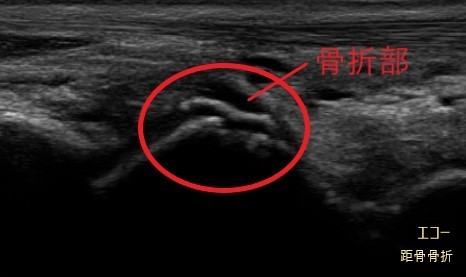

超音波(エコ-)検査は、骨・靭帯・筋肉・腱などの病態を診る検査装置です。

レントゲン画像には映りにくい筋肉や腱、靭帯などの状態に加え、骨の様子もあわせて確認できます。